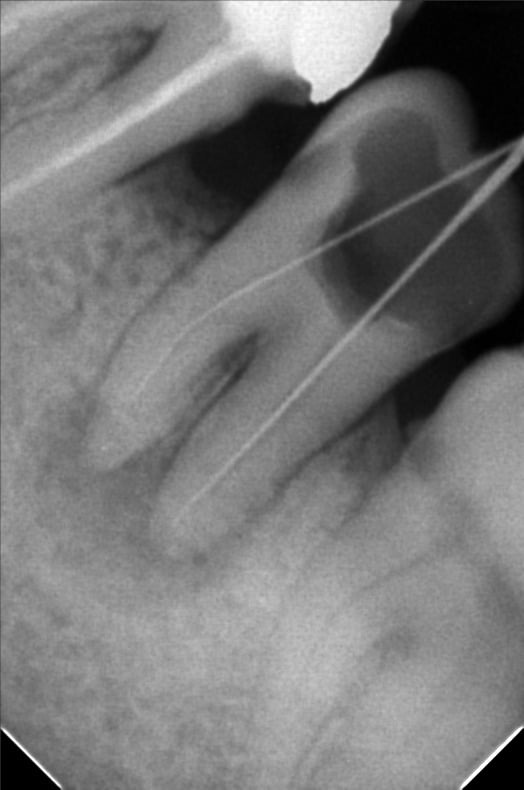

The previous dear doctor can’t located the mb canal , send me this picture

Pre operative X ray